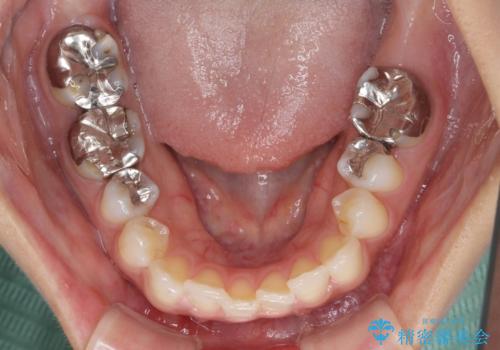

レントゲン写真などで診査した結果、奥歯の銀歯の下にはむし歯が多く存在し、右上の奥歯は歯根が破折していました。

治療開始時は右上奥歯と前歯のみが気になっていたのですが、その後下顎左右の奥歯に強い痛みや銀歯の脱離などが頻発し、問題のあるところは全て治療を行うこととしました。